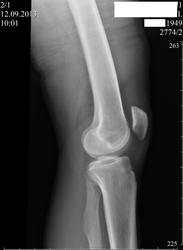

Пациент 64 года. Направлен ревматологом. Жалобы на боли в коленном суставе при ходьбе к концу дня.Ухудшение 3-й день, после перегрузки.DS.Остеоартроз коленного сустава, стадия O-I .

Вызывает вопросы малоберцовая кость. Что это? Состояние после перелома?

А углообразная деформация малоберцовой кости? то же вариант нормы?

Старый сросшийся перелом верхней трети диафиза малоберцовой кости. ДОА не вижу.

Момент травмы голени не помнит.Хотя теоретически могла быть в детстве или опроная функция не страдала, мог срастись без лечения.

А это, случаем, не луковичный периостит...как то в прямой проекции близко к тому, хотя боковая...

Виктор Григорьевич, у меня то же были сомнения в плане, не периостит ли это?  Допустим, что это периостит, а за счёт чего тогда углообразная деформация  малоберцовой кости?

Да, но структура в этом самом деформированом участке весьма "стремная".

экзостоз на широком основании. нет периостита

Добавлены архивные снимки. Такое впечатление, что за год отсутствует существенная динамика.